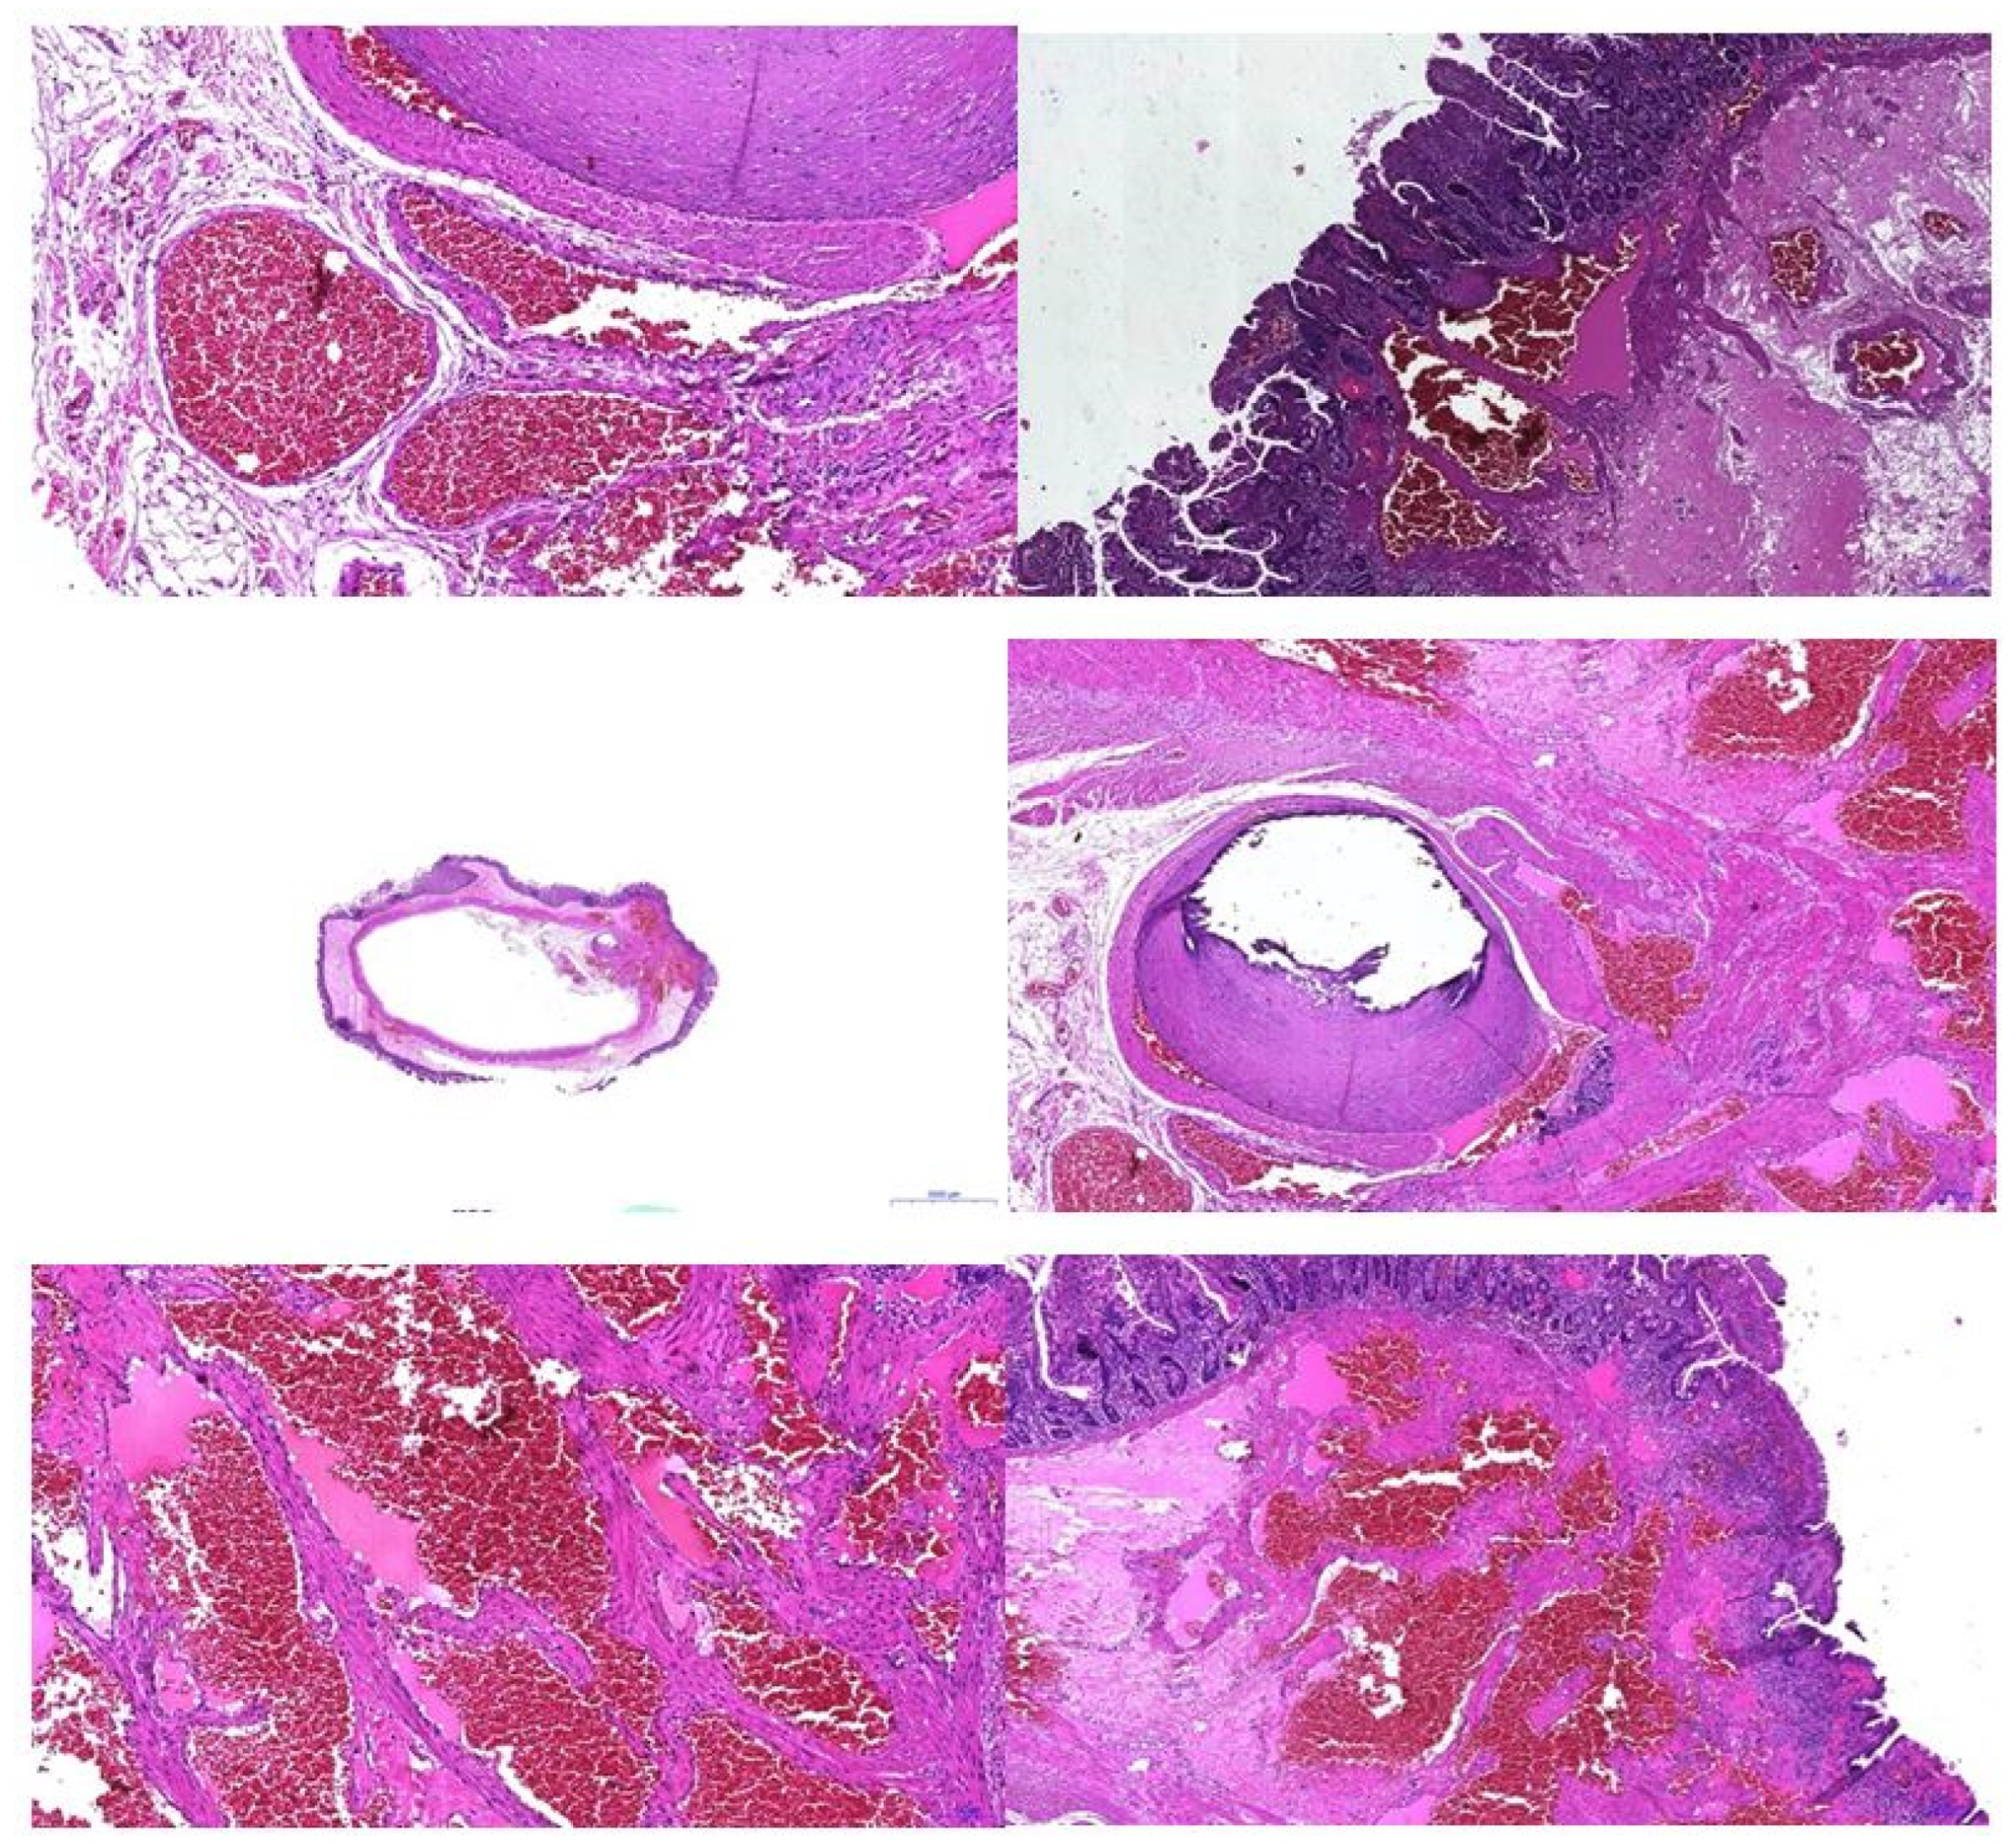

2. Detailed Case Description